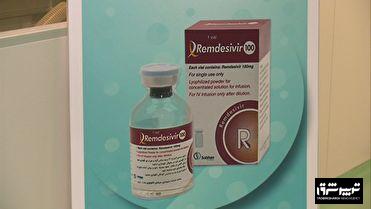

بزرگترین خط تولید داروی موثر در درمان کرونا در ایران در شرکت سبحان آنکولوژی رشت راه اندازی شد.

مدیرعامل گروه دارویی برکت وابسته به ستاد اجرایی فرمان امام(ره) در مراسم رونمایی از این خط تولید در شرکت سبحان آنکولوژی در شهر صنعتی رشت گفت: داروی رمدسیویر داروی ضدویروس کرونا است که در این شرکت بر پایه استانداردهای جهانی تولید می شود.

مدیرعامل شرکت سبحان انکولوژی هم گفت: همزمان با سال جهش تولید و در راستای عمل به این شعار، داروی رمدسیویر در شرایطی که جهان درگیر پاندمی بیماری کروناست تولید و به بازار عرضه می شود.

عنابی افزود : پیش از این این دارو را ایران و هند بصورت مشترک تولید می کردند.